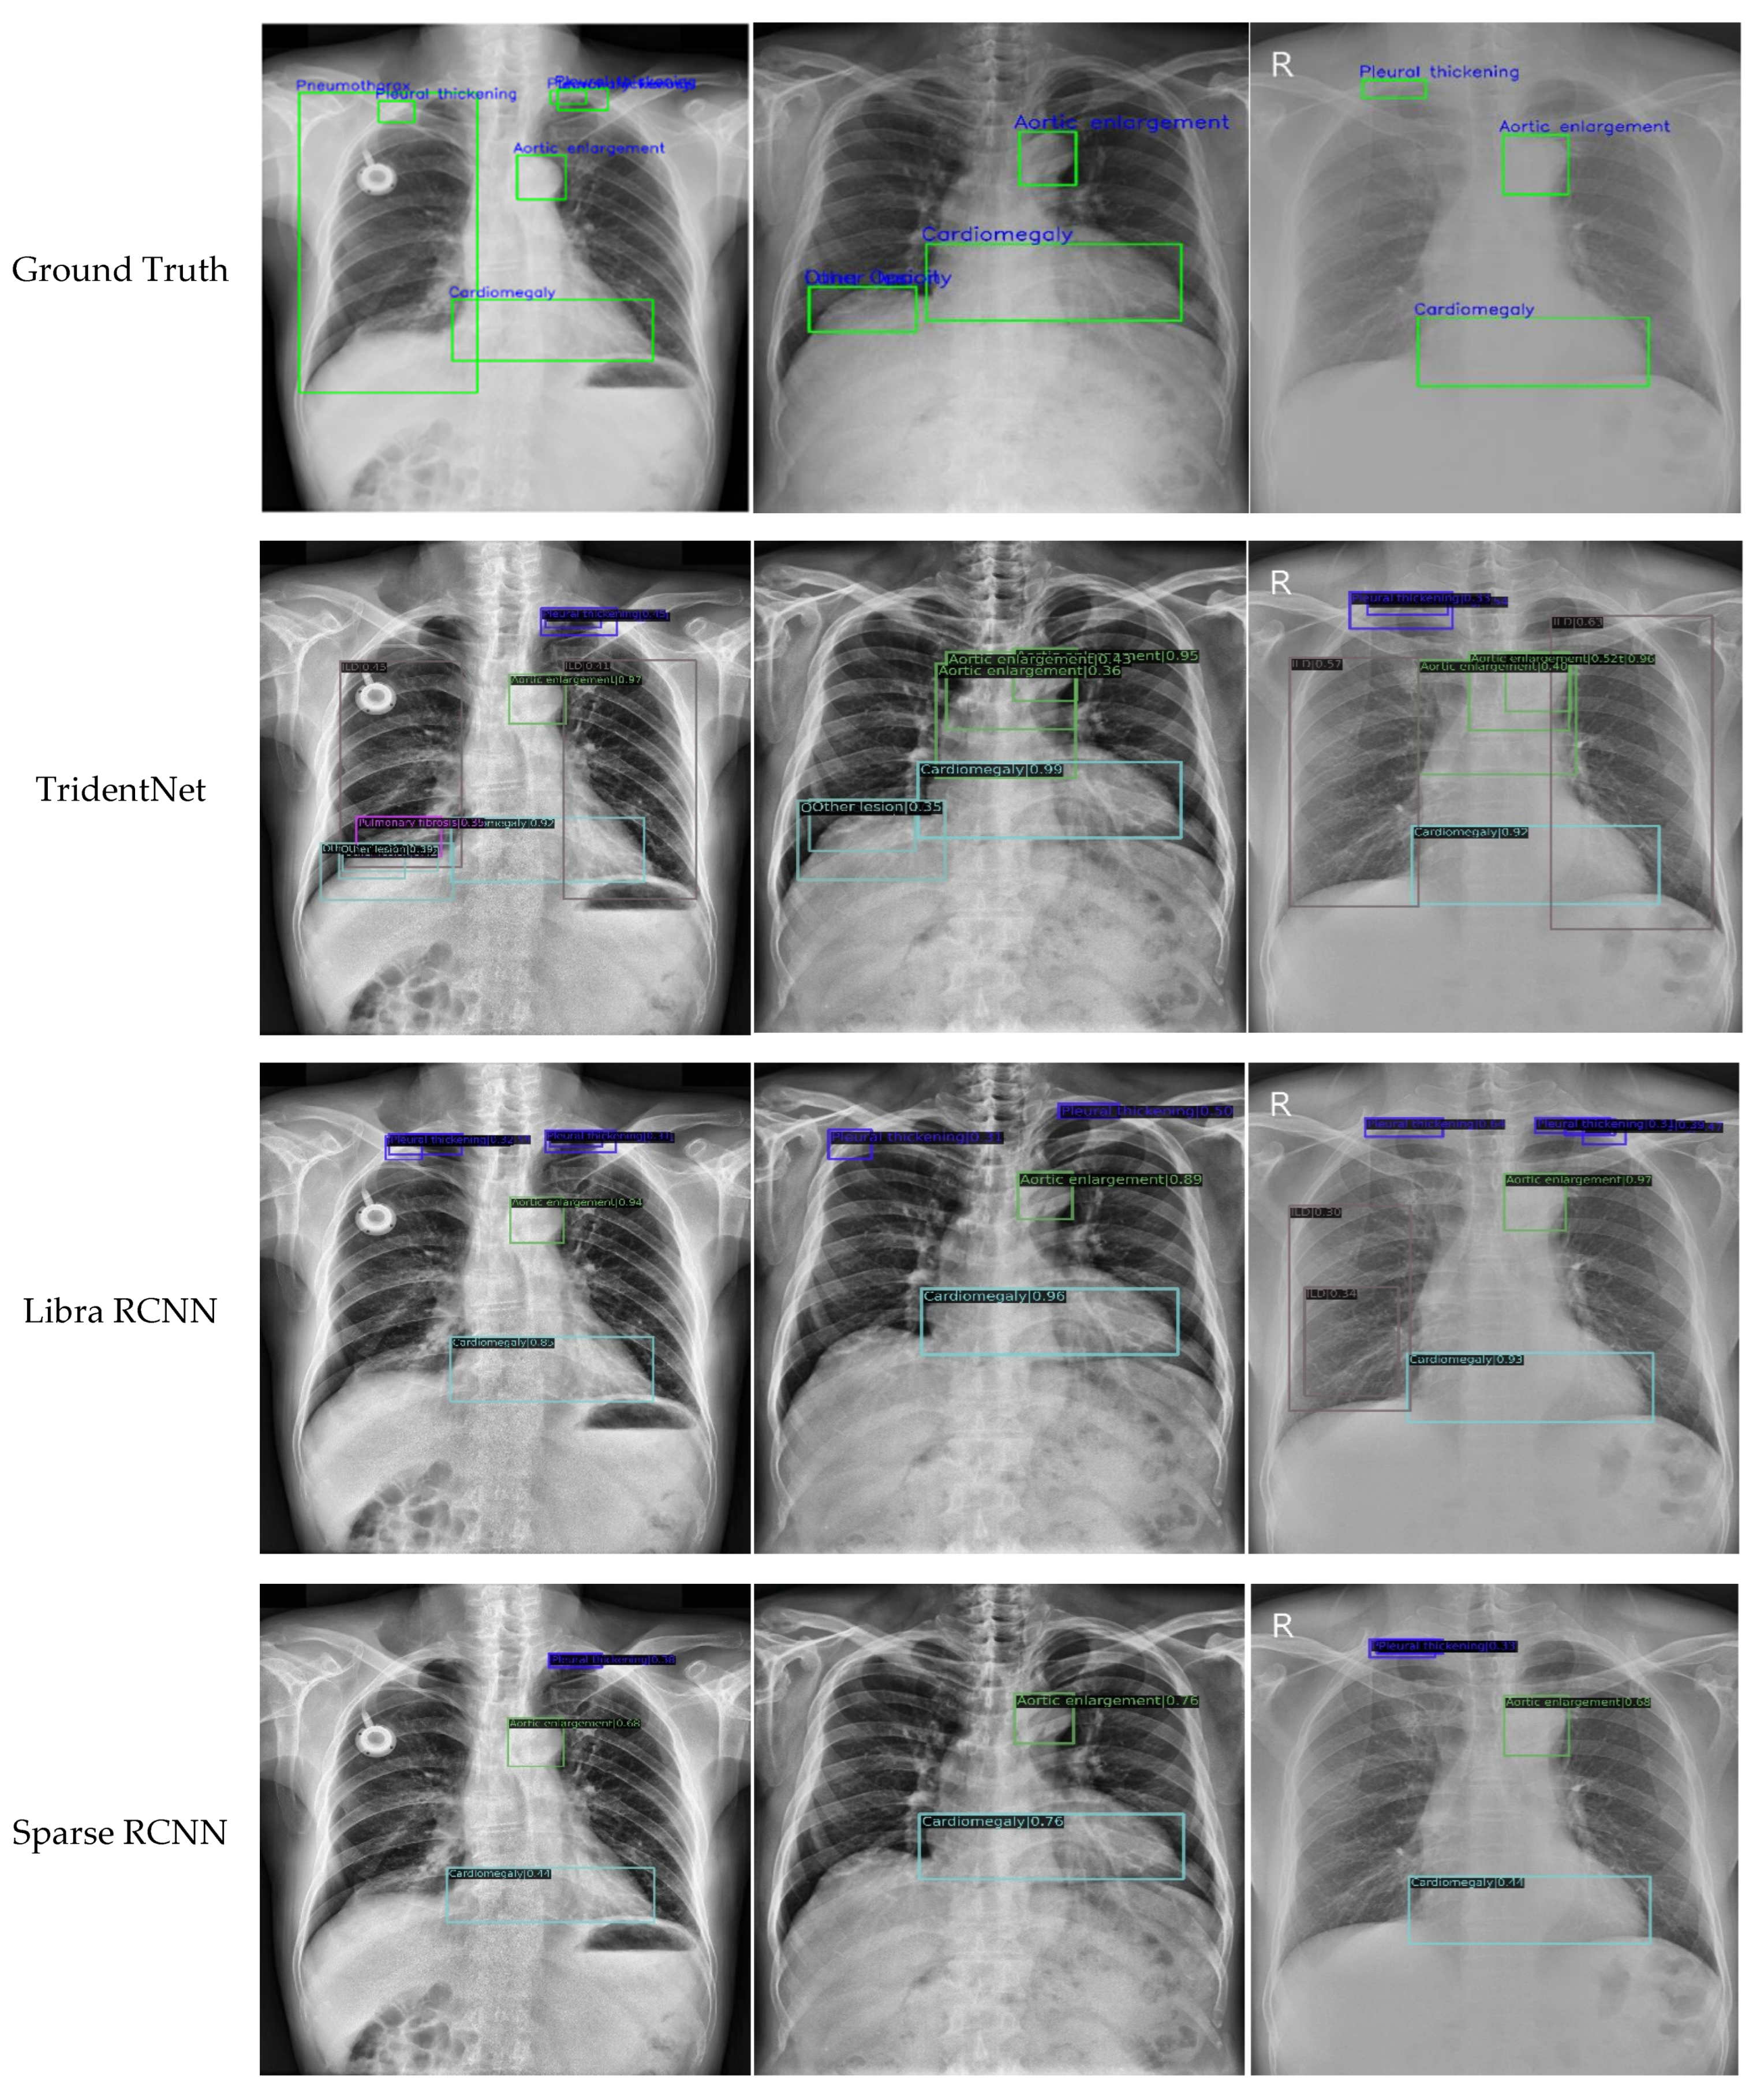

4.3. Comparison with the Latest Methods